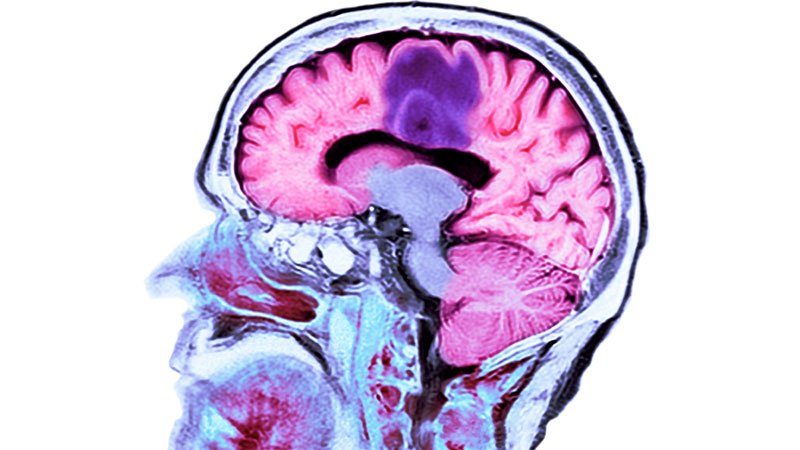

Pituitary Tumors

A pituitary tumor is an abnormal growth in the pituitary gland. This is a small gland that sits at the base of your brain behind your sinuses and above the roof of your mouth. It is connected to the hypothalamus. Both the hypothalamus and pituitary gland play important roles in your body. Most pituitary tumors, called adenomas, are not cancer (benign). However, due to their location, it takes a high level of expertise and skill, leading-edge technologies and minimally invasive techniques, including endonasal surgery, to treat pituitary tumors.